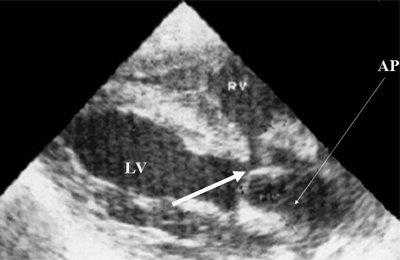

Характерными особенностями выраженной объемной перегрузки правого желудочка являются дилатация желудочка, при которой толщина миокарда не превышает верхней границы нормы, увеличение правого предсердия, парадоксальный характер движения межжелудочковой перегородки и увеличение амплитуды движения трикуспидального клапана (рис. 2, 3).

Рис. 2. Длинная ось сердца. Объемная перегрузка правого желудочка при дефекте межпредсердной перегородки. Объем сброса крови превышает 200% МОС. Отмечается выраженная дилатация правого желудочка.

Рис. 3. Объемная перегрузка правого желудочка при дефекте межпредсердной перегородки. В- и М-сканирование. Стрелкой показан парадоксальный характер движения межжелудочковой перегородки.

Для левого желудочка признаком объемной перегрузки являются увеличение полости левого предсердия и желудочка, а также экскурсии межжелудочковой перегородки и миокарда задней стенки левого желудочка (рис. 4).

Рис. 4. Объемная перегрузка левых отделов сердца. В- и М-сканирование. Отмечается усиление экскурсии межжелудочковой перегородки и миокарда задней стенки левого желудочка.

IVS - межжелудочковая перегородка, MLV - миокард левого желудочка, LV и RV - левый и правый желудочек.